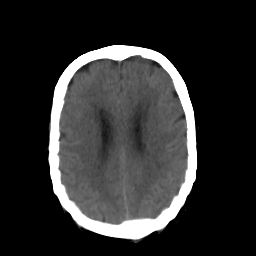

In this paper, we propose a bidirectional learning model, known as dual contrast cycleGAN (DC-cycleGAN), for medical image synthesis from unpaired data. Specifically, a dual contrast (DC) loss is formulated that leverages the advantage of samples from the source domain as negative samples to indirectly build constraints between real source and synthetic images via discriminators, and synthesize images more related to the target domain by enforcing the synthetic images to fall far away from the source domain. In addition, structural similarity index (SSIM) [35] and cross-entropy (CE) [48] are integrated into the DC-cycleGAN structure to avoid disappearing gradient information that is caused by a mean absolute error (MAE) and synthesizing irrelevant images. SSIM considers luminance [35] and CE converges fast as its back-propagation error is less than MSE [28]. As can be seen in Figs. 1 and 2, using SSIM and CE with dual contrast can generate more clear and accurate MR images as compared with that of MAE and MSE, and SSIM and CE without dual contrast loss. Although both SSIM and CE with dual contrast and without dual contrast generate similar CT images, SSIM and CE with dual contrast quantitatively generate better images as shown in Table 4. The experimental results indicate that DC-cycleGAN is able to consider more complex features such as structure in synthesizing images and produce remarkable results as compared with other state-of-the-art methods reported in the literature.

Tables 3 and 4 show the results of MR and CT synthesis, respectively. As can be seen, all components play vital role in both tables. SSIM & CE (w) performs significantly better than other losses in synthesizing MR images. This also can be seen visually in Fig. 1. In contrast, SSIM&CE (w) performs slightly better than SSIM&CE (wo) in synthesizing CT images, both generate more or less similar CT images (see Table 4).